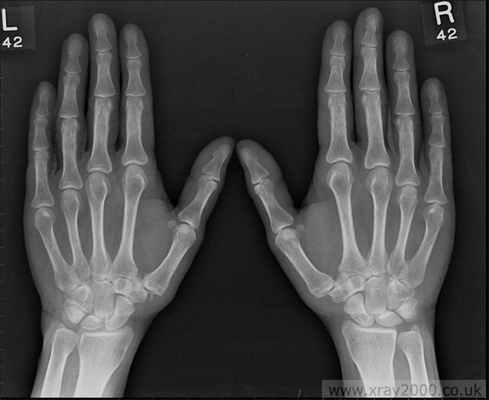

Остеоартроз мелких суставов кисти

Характеризуется следующими клиническими признаками:

- Наличие плотных узелков на боковых поверхностях дистальных межфаланговых суставов (узелки Гебердена) и на тыльно-боковой поверхности проксимальных межфаланговых суставов (узелки Бушара); Образование узелков сопровождается жжением, покалыванием, онемением (после завершения формирования узелков эти симптомы исчезают)

- Боль и некоторая скованность в суставах кисти, уменьшение объема движений.

- Прогностически наличие узелков Гебердена или Бушара является неблагоприятным признаком течения остеоартроза. (эта форма остеоартроза имеет генетическую детерминированность и передается по женской линии).

Остеоартроз пястно-запястного сустава большого пальца

Этот вид остеоартроза наблюдается, как правило, у женщин климактерического возраста чаще всего двухсторонний и проявляется болями в месте сочленения пястной и трапециевидной кости при совершении движений в большом пальце кисти. Кроме того возможно ограничение в объеме движений и хруст. При выраженном остеоартрозе возможна значительная деформация кисти. Но обычно для этой формы остеоартроза не характерны выраженные болевые проявления и нарушения подвижности.